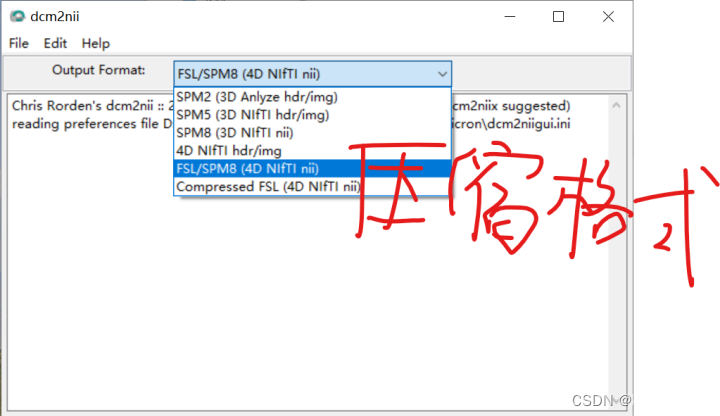

N:格式转换,把存储原始fMRI信息的数据转换为NIFTI格式

(1)首先是格式转换:使用dcm2niigui,将原始数据文件夹整个拖进去

或者使用microGL(既可看图又可转换文件)